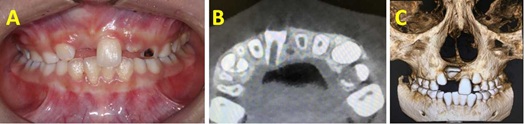

The apical foramen of impacted malformed central incisor was not closed, guided eruption combined with surgical exploration was possible. Lingual button was bonded on lingual side of the incisor during surgical flap operation. The patient was recalled after 1 week and orthodontic traction was taken. Removable appliances was used for 3 months. Interactive traction was used for 2 months. Fixed orthodontic treatment was planned to align the upper anterior teeth for 3 months (Figure 2). Lingual retainer was bonded from letaral incisor to letaral incisor (Figure 3).

Figure 3 (A to C): 3A) Intraoral photograph after treatment (B to C) Panoramic radiography and CBCT showing the correct position of incisor.